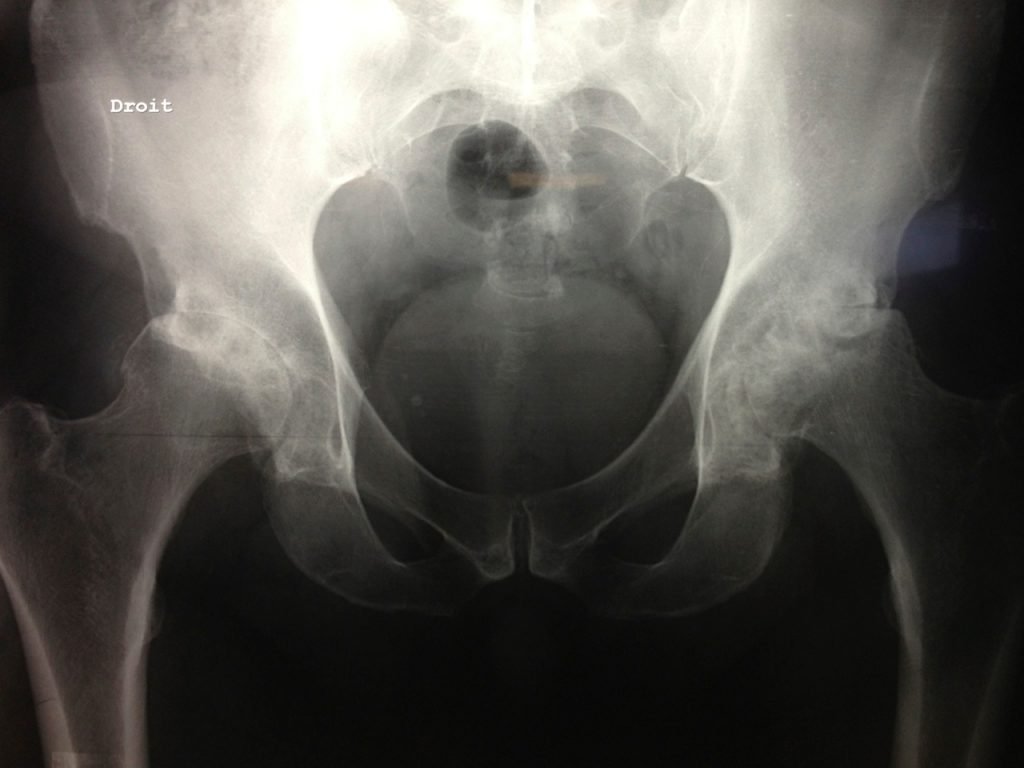

Un bilan radiographique complet est réalisé permettant de confirmer le diagnostic et de prévoir la chirurgie.